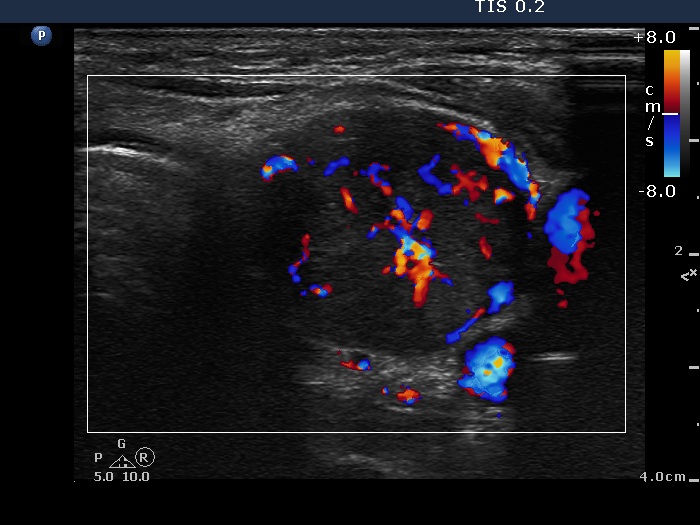

Ultrasonography: The right lobe was hypoechogenic, the left was moderately hypoechogenic. Both lobes were irregular in shape and were composed of several circumscribed areas surrounded with echonormal rim. The vascularization was significantly increased.

The sonographic pattern is specific. At first sight both lobes, particularly the right one seems to be nodular. First, the lobes are composed of a central hypoechogenic part surrounded with an echonormal rim, therefore it seems like the lobes were composed of a large hypoechogenic nodule. Second, connective tissue, perhaps a scar makes an impression in the ventral and in the dorsal part of the right and the left lobe, respectively. This makes an appearance as the lobes were composed of two nodules or one lesion with irregular lobulated and spiculated margins. In fact, the scar is responsible for the irregularities seen on the surface of the hypoechogenic mass, and regarding the hypoechogenic mass, the inclinations are the primary cause.